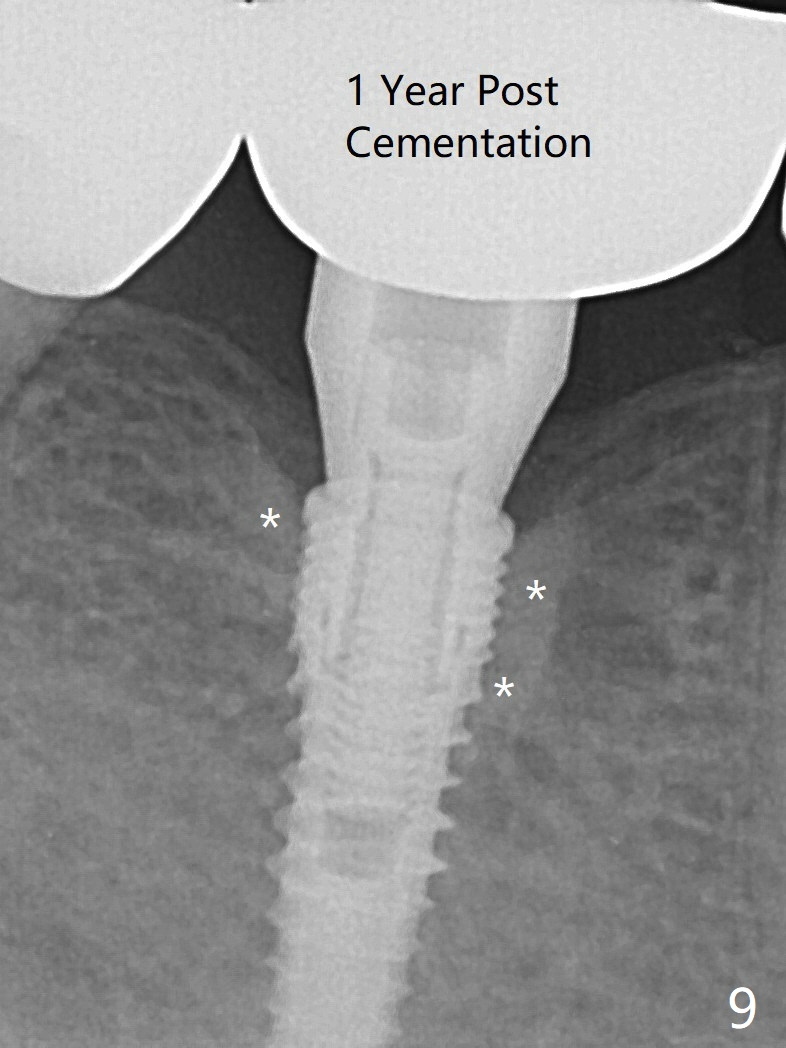

When a 3.8x12 mm SM implant is placed with 40 Ncm, there is 1-2 mm cortical bone buccolingually (primary stability, Fig.4,5). The thick cortices do not seem to be easy to be bent, i.e., expanded. There appears dense bone formation 3 months postop (Fig.8 *). One year post cementation, the crown at #31 needs recementation (Fig.9); the bone density next to the coronal implant increases (*).